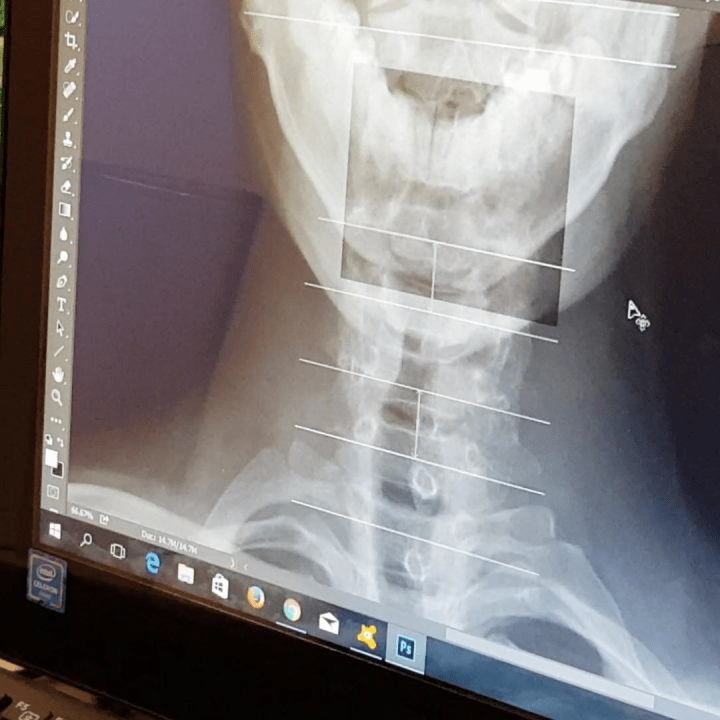

Mabuhay Chiropractic Clinic does a very thorough spinal check first using an X-RAY to verify spinal mis-alignment to help pinpoint the reason for the pain you are experiencing before doing the actual alignment.